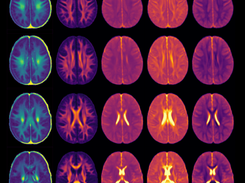

Atlas is described in this paper: https://onlinelibrary.wiley.com/doi/full/10.1111/jon.12689. Structural template, myelin water fraction, fractional anisotropy, mean diffusivity, radial diffusivity and axial diffusivity atlases for children aged 9-10 years are provided for free download for pediatric neuroimaging applications.